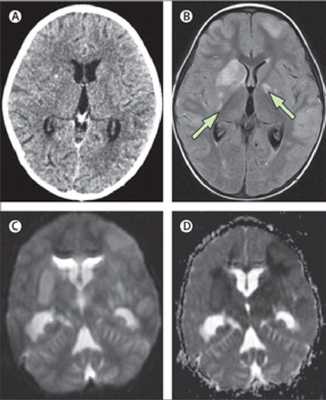

(A) нормальный мозг по данным КТ, 3х-летний ребенок с подтвержденным туберкулезным менингитом. (B)Т2-взвешенные изображения с подавлением сигнала от свободной жидкости, проведено в тот же день, что и КТ, на 5ыйдень выраженных клинических проявлений, показывают несколько инфарктов (стрелки) в области базальных ядер. Диффузно взвешенные МР изображения (С, D) показывают, ограничение диффузии в области базальных ядер.

Туберкулезный менингит с изменениями оптико-хиазмальной области. МРТ

(A) Т1-взвешенное изображение после в/венного контрастного усиления препаратом гадолиния,7 -летний мальчик со значительным субтотальным снижением зрения, вызванным тяжелым туберкулезным менингитом, с изменениямиоптико-хиазмальной области показывает повышение интенсивности МР-сигнала на фоне накопления контрастного вещества утолщенными оболочками практически всей супраселлярной цистерны со смещением и компрессией зрительного нерва спереди. Накопление контраста в виде кольца стенкой туберкулезного абсцесса.

(В) После 3 месяцев адъювантной терапии зрение пациента восстановилось и при последующих МРТ определяется существенное улучшение оптико-хиазмального арахноидита несмотря бессимптомное увеличение размеров абсцесса и появление дополнительных очага и фокуса абсцедирования.